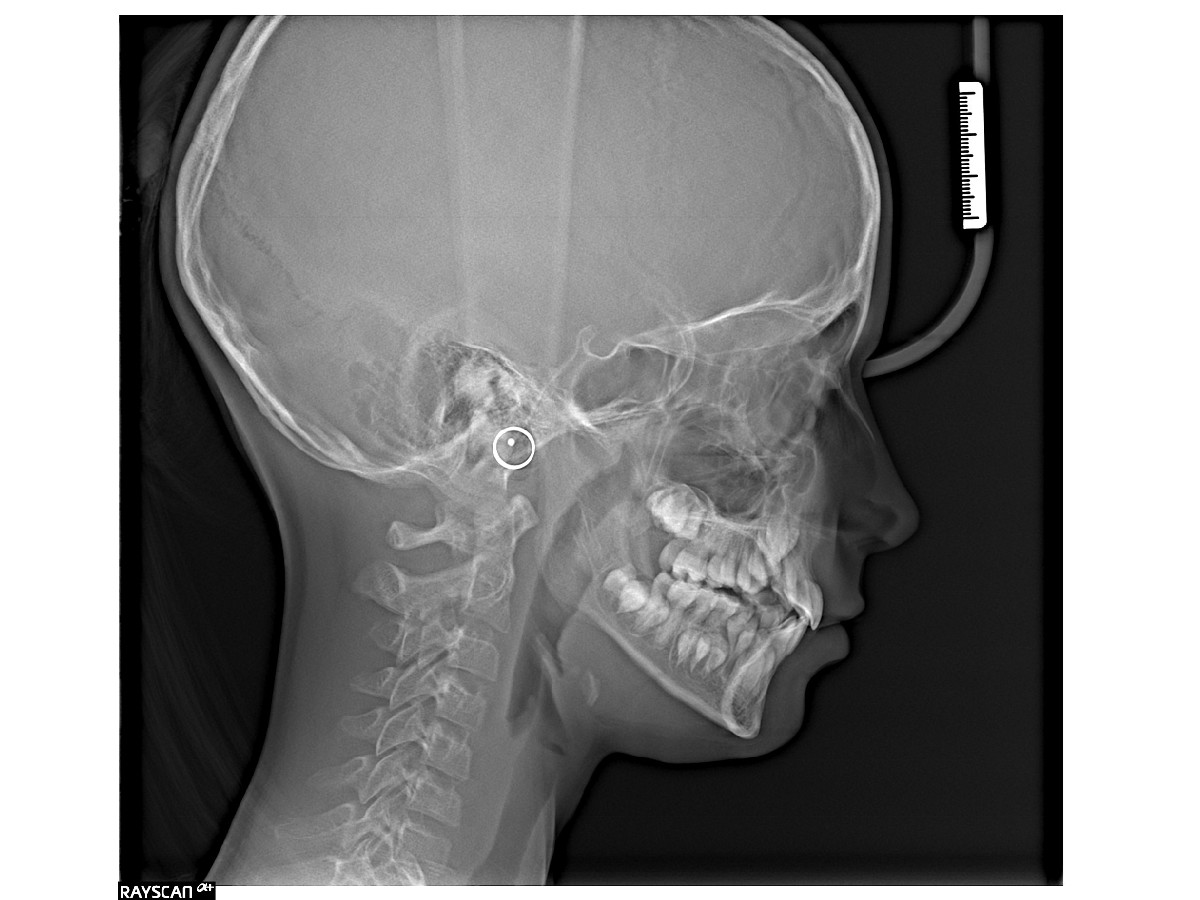

Cefalometria to rodzaj rentgenowskiego zdjęcia z możliwością dokładnej analizy budowy twarzoczaszki, układu zgryzu i proporcji twarzy. Wykonywane jest ono w projekcji bocznej lub przednio-tylnej, umożliwiając ocenę wzrostu kości oraz planowanie leczenia ortodontycznego i chirurgicznego. Zdjęcie uzyskuje się za pomocą cefalostatu. Obraz zostaje następnie poddany cyfrowej analizie, pozwalając na precyzyjne pomiary i diagnostykę.

Zdjęcia cefalometryczne wykonuje się przede wszystkim w diagnostyce i planowaniu leczenia ortodontycznego. Pozwalają one ocenić układ kostny twarzy, relację szczęki do żuchwy oraz wzrost i rozwój struktur kostnych. Są niezbędne przed rozpoczęciem leczenia aparatami stałymi i ruchomymi, a także do monitorowania postępów terapii. Stosuje się je również w leczeniu okluzji do oceny wad zgryzu oraz w chirurgii szczękowej przed zabiegami rekonstrukcyjnymi.

Cefalometria jest wykorzystywana w diagnostyce problemów laryngologicznych, np. bezdechu sennego, gdy zachodzi konieczność analizy drożności dróg oddechowych. Wskazaniem może być także podejrzenie asymetrii twarzy lub zaburzeń wzrostu kości.